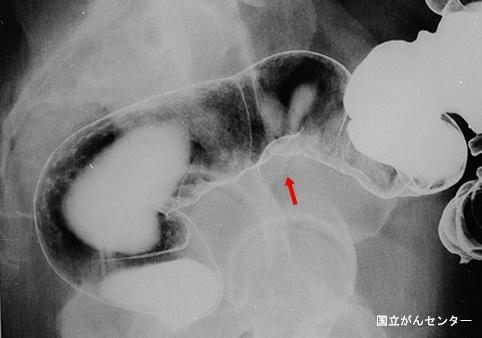

Mixoma (mucocele) maligno de la apéndice cecal acompañado de adenoma pseudomucinoso del peritoneo

Otros Tumores/Mucocele Apendicular Maligno

colon/sigmoides

Rayos X

25 - 29